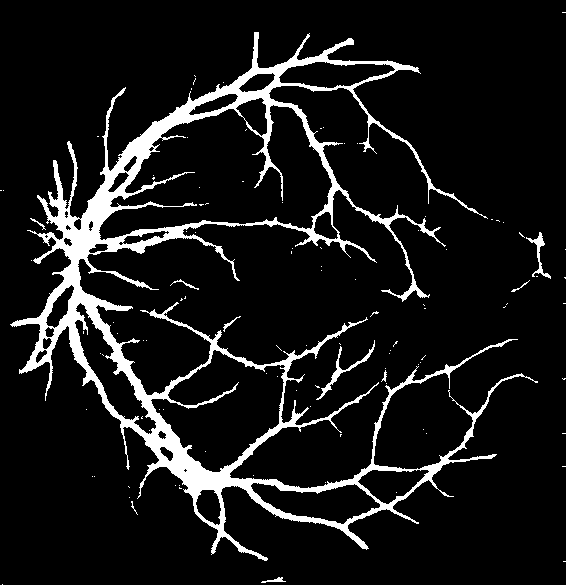

Figure 5: Visual results after level I balancing. The level I balancing increases the patches for vessel representation.

Impact of Level-I Balancing: Table I illustrates the performance of the CNN before and after applying Level-I and Level-II balancing on a couple of randomly sampled images from the DRIVE dataset. It should be noted that the proposed CNN is quite naïve in the absence of Level-I balancing (as evidenced by quite low sensitivity value). CNN favors non-vessel pixels, as it is the dominant class. However, Level-I balancing improves the sensitivity result, though specificity is a bit compromised now. However, as we will see in the next sub-section, this compromise is also normalized after the application of Level-II balancing. Nevertheless, we conjecture here that the proposed balancing algorithm augments even a simple CNN model (only ten layers) to produce state-of-the-art results. Figure 5 shows the visual results of segmenting the two sample images along with their ground truths. It can be observed in the visual analysis that the overall distinction of vessel pixels is much better after the application of Level-I balancing. However, the model is lacking in segmentation of thin vessels, even after the application of Level-I balancing. We conjecture this is due to the imbalanced distribution of thin and thick vessel pixels, which is overcome by Level-II balancing, as discussed in the next subsection.